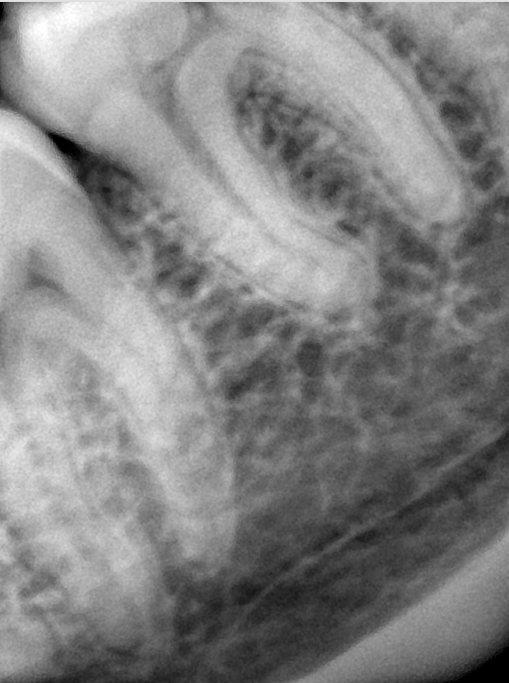

CR/DR 牙齿分割阶段记录

当前进展

- 完成了 CR/DR 牙齿相关分割训练

- 当前结果已经达到阶段预期,但仍有细节问题需要继续处理

相关测试

遇到的问题

- 训练过程中出现过 mask 下移问题

- 部分结果会出现 box 填充异常

- mask 边缘仍然有比较明显的锯齿感

参考

第二版算法问题测试